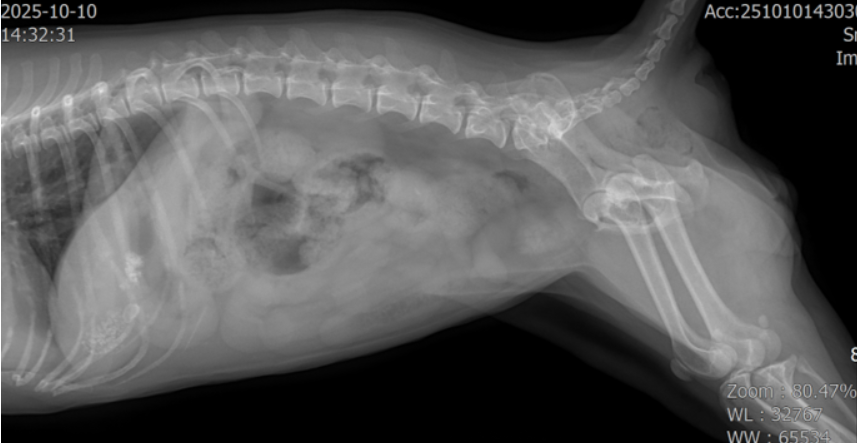

X-ray

방광(bladder) 부위에 다수의 방광결석(cystolith)이 의심되는 음영이 확인되었습니다.

Abdominal ultrasound(복부 초음파)

bladder wall(방광벽)이 두꺼워져 있어 chronic cystitis(만성 방광염)을 의심할 수 있는 소견

bladder 안에 다수의 결석(cystolith)이 확인되었고, urethra(요도) 방향으로도 여러 개의 결석이 내려가 있는 상태가 확인되었습니다.

현재 영상·혈액 소견을 종합했을 때 Urinary cystitis + bladder/urethral urolithiasis(방광염 + 방광/요도결석)에 의한 요실금, stranguria(배뇨곤란) 가능성이 가장 크게 확인되었습니다.수술적 교정

초음파에서 bladder 내 다수의 방광결석,urethra 쪽으로 내려간 결석들,bladder wall 비후(방광염 소견)가 동시에 확인되었습니다.